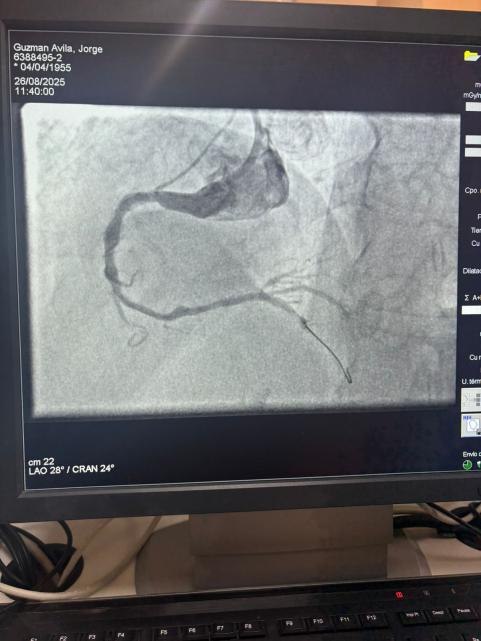

We are proud to share a remarkable case from Hospital Sótero del Río, Chile, where Dr. Martín Valdebenito successfully treated a heavily calcified lesion in the right coronary artery (first curve) using our Vesscrack Coronary IVL Balloon Dilatation Catheter System.

The procedure achieved outstanding results, with the calcified region effectively cracked and vessel flow restored. This marks another milestone in expanding global access to advanced solutions for complex coronary calcification.

The comparison between the pre-procedure and post-procedure angiographic images clearly demonstrates the significant clinical impact of our IVL technology.